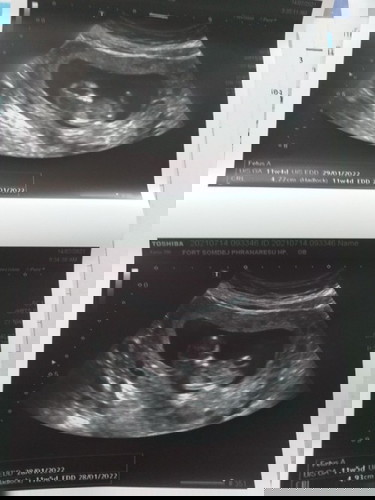

4วีคคือ1เดือนค่ะ 11วีค5วัน คือ2เดือน3สัปดาห์5วันค่ะ

ในใบซาวคือ 11 วีค นะ..นั้นแปลว่า2 เดือนครึ่ง คะ